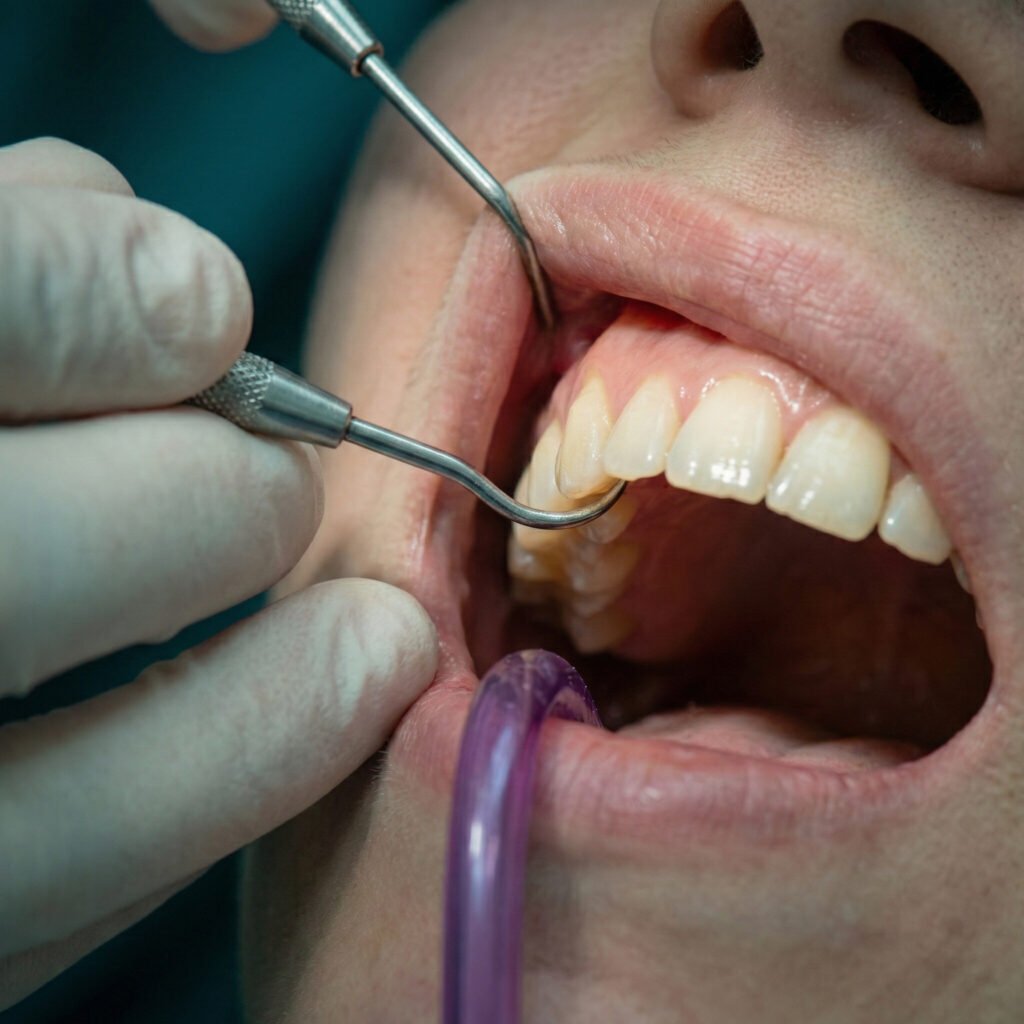

maladie parodontale

Restaurez la santé de vos gencives grâce à des traitements sur mesure ciblant les maladies gingivales.